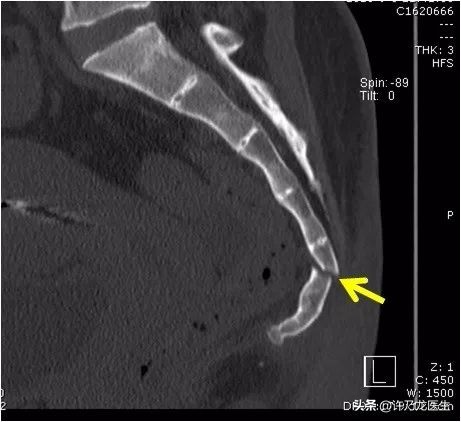

可能需要照 X 光片辅助诊断,来确定尾椎是否存在骨折或脱位。有些疑难的情况或者 X 光片无法看清的,还要拍摄 CT。